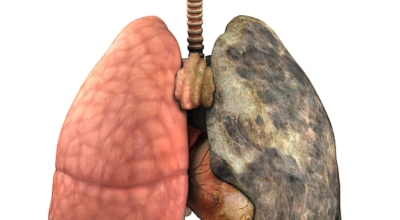

폐에 발생된 악성 종양을 말하며 오랜 기간 흡연해온 남성들에서 발병률이 높고 요즘 들어 가지가지 환경적인 요인의 영향과 간접흡연으로 흡연하지 않는 여성에서도 많이 발생하고 있어요. 증상을 느껴 병원을 찾았을 때는 수술하기 늦은 경우가 많아 사망하는 비율이 매우 높은 암입니다.

폐 자체에서 생기거나 다른 장기에서 발생된 암이 폐로 전이되어 나타나기도 하고 특별한 초기 증상이 없는 경우가 많다고 하며 암이 진행된 후에도 일반적인 감기 증상인 기침과 가래 외의 특이 증상이 나타나지않아 증상만으로는 진단이 쉽지 않아요. 폐암 역시 다른 암들과 마찬가지로 조기 발견 및 치료가 매우 중요하므로 일상 속에서 폐암 초기증상을 간과하지 않도록 주의를 기울여야 해요.